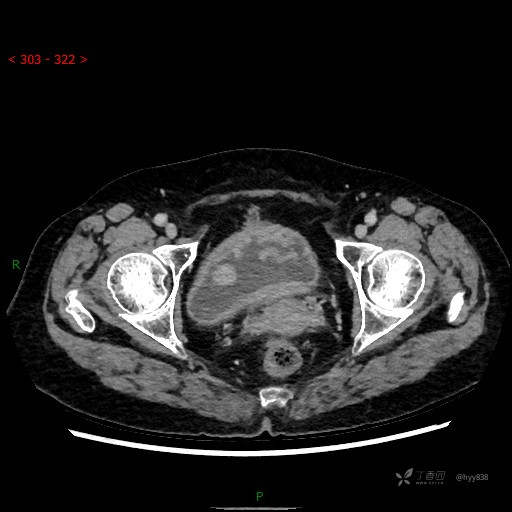

膀胱少见肿瘤,欢迎挑战---结果公布~

华夏览雄 达人已点赞患者性别:女

患者年龄:73岁

主诉:肉眼血尿3周

简要病史:患者诉3周前无明显诱因开始出现肉眼血尿,发作时尿液呈鲜红色,为全程血尿,无明显血凝块;伴小腹胀痛,无尿频、尿急、尿痛;无寒战、发热;无恶心、呕吐,就诊于当地医院行输液治疗后,出现不规则血凝块,进一步完善相关检查提示膀胱占位,活检提示膀胱炎性改变,现患者为进一步治疗,遂来我院,门诊以“膀胱肿物”为主诉入院。 起病以来,患者精神、饮食、睡眠稍差,大便如常,小便如上述,近期体力、重无明显变化

临床诊断:膀胱肿瘤

膀胱CT平扫(2022.10.20)

增强(2022.11.1)